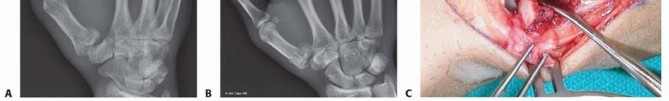

Closed Reduction and Percutaneous Pinning (CRPP)

CRPP is the treatment of choice for classic Bennett fractures where the volar-ulnar fragment is too small to reliably accept a lag screw, yet the joint can be anatomically reduced closed. The reduction maneuver is highly specific, designed to counteract the deforming forces of the APL and Adductor Pollicis. Longitudinal traction is applied to the thumb, followed by palmar abduction and pronation. Direct pressure is then applied to the dorsal-radial aspect of the metacarpal base, effectively pushing the shaft back into the anatomic cradle of the intact volar-ulnar fragment.

Once anatomic reduction is confirmed via multi-planar fluoroscopy, percutaneous fixation is achieved. Typically, two 0.045-inch or 0.062-inch Kirschner wires are utilized. The first wire is driven from the dorsal-radial aspect of the metacarpal shaft directly into the trapezium, effectively neutralizing the proximal pull of the APL. A second wire is often placed transversely from the first metacarpal shaft into the second metacarpal to control rotation and maintain the web space. Pins are cut outside the skin and capped to facilitate easy removal in the clinic.

Open Reduction and Internal Fixation (ORIF) - Wagner Approach

For fractures with large volar-ulnar fragments (>20% of the articular surface), displaced Rolando fractures, or cases where closed reduction fails, ORIF is unequivocally mandated. The classic Wagner approach provides unparalleled exposure to the thumb CMC joint. A curvilinear incision is made along the glabrous border of the thenar eminence, curving dorsally at the level of the CMC joint.

Meticulous superficial dissection is required to identify and protect the sensory branches of the superficial radial nerve dorsally and the palmar cutaneous branch of the median nerve volarly. The thenar musculature (abductor pollicis brevis and opponens pollicis) is sharply elevated from the metacarpal shaft and retracted volarly. The joint capsule is then incised longitudinally or in an L-shaped fashion to expose the articular surface. The hematoma is evacuated, and the fracture fragments are meticulously debrided of interposed soft tissue.

For a large fragment Bennett fracture, the shaft is reduced to the volar-ulnar fragment using a pointed reduction clamp. Provisional fixation is achieved with a K-wire. A 1.5mm or 2.0mm lag screw is then placed perpendicular to the fracture plane. The near cortex must be overdrilled (gliding hole) and the far cortex underdrilled (thread hole) to achieve true interfragmentary compression. The screw head should be countersunk to prevent hardware prominence beneath the thenar muscles.